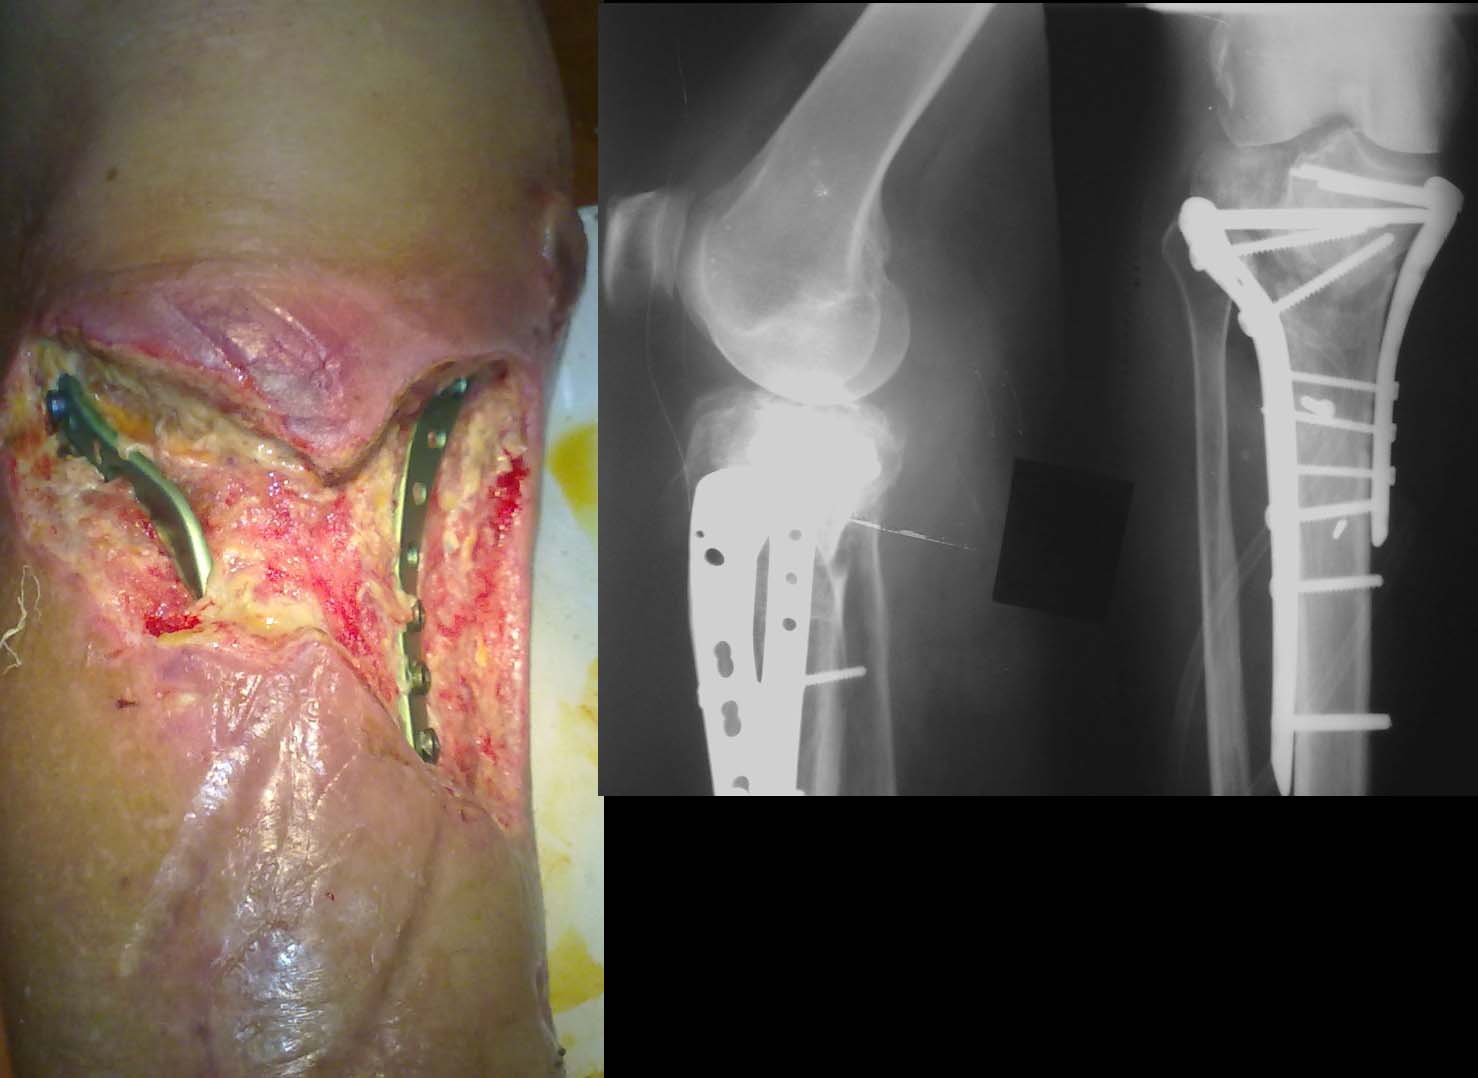

П-ка К. 57 лет, страдает инсулинозависимым сахарным диабетом в течение 10 лет,оперирована

03 09 12,на данный момент имеется такая картина. Сахара компенсированы, получает системно

а.б. препараты по посеву, ГБО. В течение недели, пока ожидали результат посева,

использовали NPWT, сустав пока не пунктировали. Возможно ли использование вакуумной

повязки, учитывая возбудитель (Klebsiella pneumoniae)? Стоит ли сейчас удалять фиксаторы

с заменой на АВФ? Какие еще эффективные мероприятия посоветуете предпринять? Спасибо за